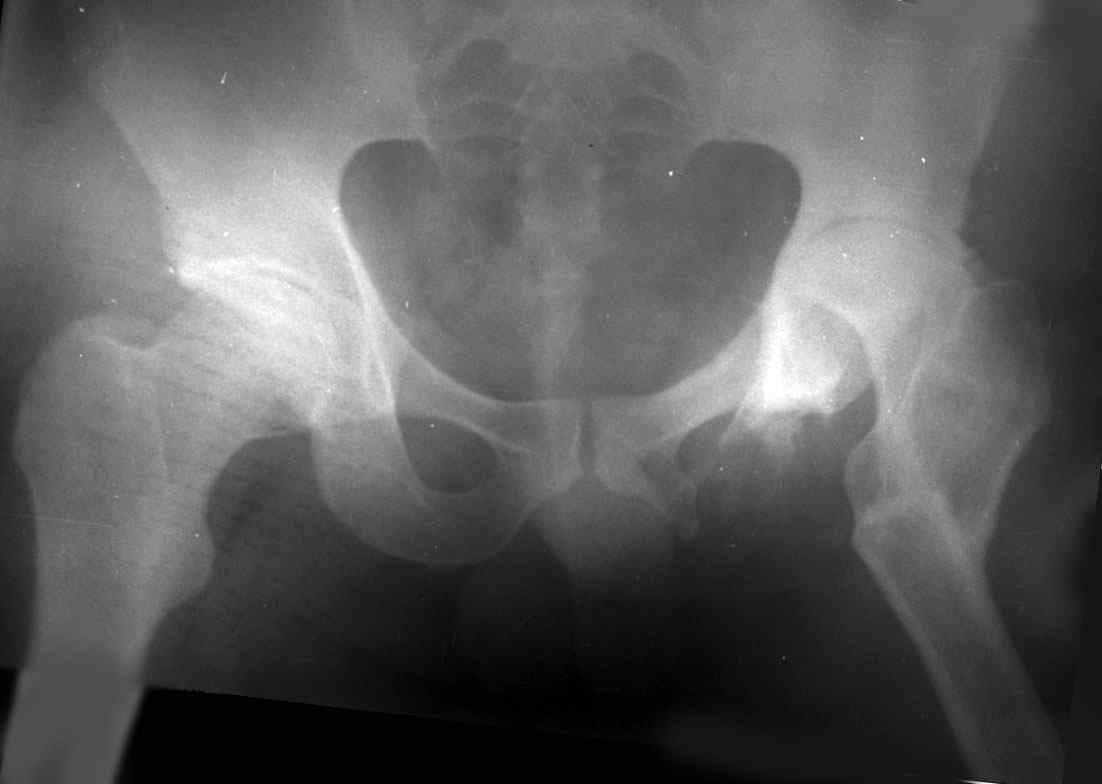

остеотомии. Я представил Р-граммы больных с неудачными р-ми после остеотомий.

Эндопротезирование у них было на порядок сложнее в отличие от артропластики без проведения остеотомии.

.........наверное не повезло. Но иногда это выход и очень хороший. М., 21 года спрыгнул в Армии с машины с исходом в гнойный коксит, свищевой формой в течении 1,5 лет. Операция проведена в 1988 году. результат хороший и сейчас и мы с пациентом хорошие приятели (Рентг-гр и фото прилагаю).

Вы немножко не поняли предмета нашего разговора. На представленных Вами Р-граммах речь идет о вальгизирующих остеотомиях, скорее всего в

комбинации с разгибанием... Никто и не оспаривает полезность этих остеотомий, мой личный опыт свидетельствует о том, что даже при

выраженной стадии коксартроза у лиц молодого возраста существенно снижается болевой с-м, ремиссия иногда достигает 12-16 лет, а там уже не

грех и протез поставить.

На обсуждение поставлен вопрос об эффективности опорной остеотомии по Илизарову (как правило), при врожденных вывихах бедра. Почувствуйте разницу...